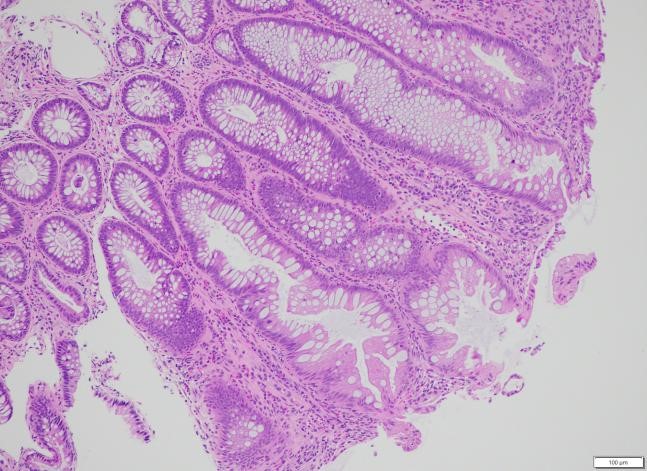

Kết quả mô bệnh học

Trên 04 tiêu bản làm từ bệnh phẩm nhận được, nhuộm HE và PAS thấy:

Ống 1 (đại tràng): Có 03 mảnh sinh thiết niêm mạc đại tràng nhỏ, bề mặt phẳng, tuyến chế nhầy bình thường về số lượng và hình thái. Mô đệm giữa các tuyến phù nề nhẹ, thâm nhiễm rải rác tế bào viêm mạn tính số lượng ít. Không phát hiện dị sản, loạn sản, ung thư, polyp, hình ảnh lao, nấm hay bệnh Crohn.

Ống 2 (đại trực tràng): Niêm mạc dày nhẹ, tuyến chế nhầy có vùng kéo dài nhẹ nhưng vẫn lành tính. Biểu mô phủ có vùng thoái hóa, bong trợt. Mô đệm xen giữa các tuyến thâm nhiễm nhiều tế bào viêm mạn tính và bạch cầu đa nhân trung tính, rải rác có nang lympho. Không thấy dị sản, loạn sản, ung thư, polyp hay viêm đặc hiệu.

Hình 3: Hình ảnh giải phẫu bệnh nhuộm Hematoxylin-eosin x 100